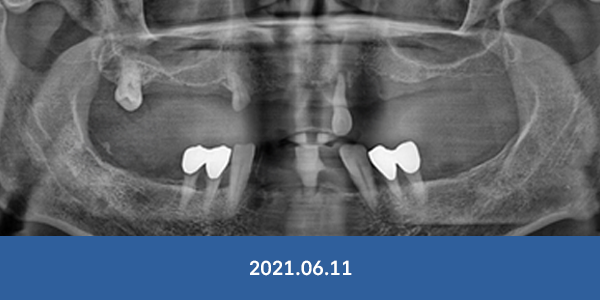

이정웅 대표원장

임플란트 식립 개수

연간 3천개

최근 6년 임플란트 식립개수 누적 1만3천개 돌파

임플란트 수술, 경험이 곧 실력입니다.

임플란트 부작용, 더는 걱정마세요!

개원 이래 대학병원 전원율 0% 달성

※ 서울감동치과에서 실제 수술 받으신 환자분들의 사진입니다.